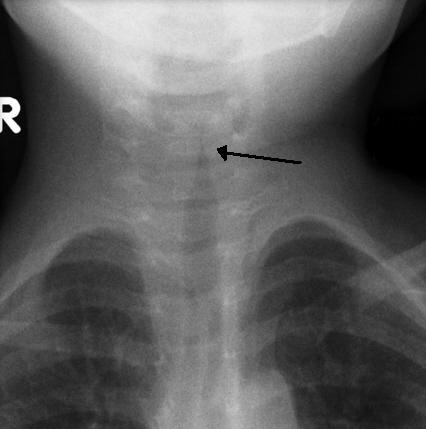

크룹(후두기관지염)은 성대의 바이러스 감염으로, 일반적으로 5~6일 지속된다. 주요 증상은 짖는 듯한 기침과 저열이다. X선 사진에서 크룹은 기관의 협착을 나타내는 "첨탑 징후"로 확인할 수 있다.

3개월에서 5세 사이의 어린이에게 겨울철에 가장 흔하게 발생한다. 세균에 의해 발생하는 심각한 형태는 세균성 기관지염이라고 한다.[11]